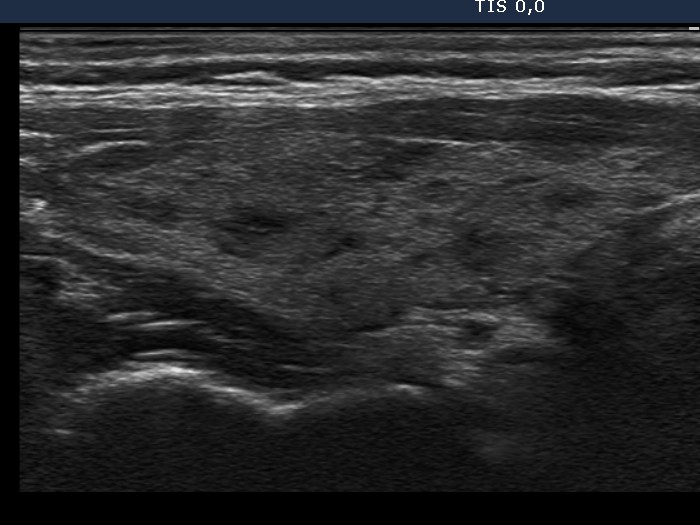

Graves' disease - Case 11.

Five weeks after the first visit (ultrasonographic

picture 2)

Right lobe, longitudinal scan.